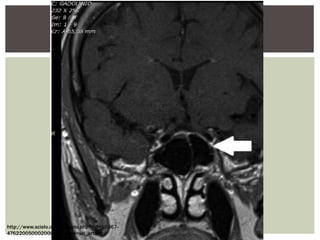

La imagen

característica es la de

"silla turca vacía",

la cual aparece varios

meses posteriores al

evento hemorrágico.

 La tomografía computarizadao una resonancia magnética usualmente no son útiles en la fase aguda.

La imagen característica esla de "silla turca vacía", la cual aparece varios meses posteriores al evento hemorrágico. Síndrome de Sheehan en una mujer de 37 años de edad que presentó con una historia clásica de hipopituitarismo de 3 meses de evolución luego de un parto complicado. La imagen de una MRI T1, un corte Sagital, muestra un silla turca vacía con herniación del quiasmo óptico (flecha) en la silla turca.